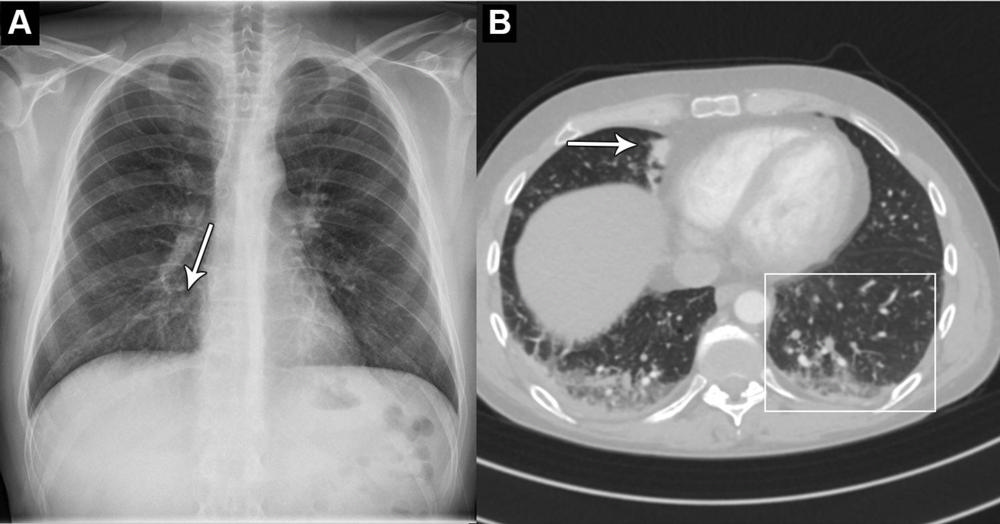

Figure 5. Images in a 44-year-old man who presented with chest pain and dyspnea. (A) Chest X-ray shows very subtle nodular opacities, primarily in lower lobes, representative of pneumonia and a discrete silhouette sign of the right cardiac border (arrow). The AI system interpreted this chest X-ray as normal. It was also interpreted as normal in the clinical radiology report. (B) CT scan shows the lower lobe airspace opacities with vague tree-in-bud morphology (box) and an area of consolidation (arrow). Pulmonary angiography was performed 5 hours after X-ray. This was the sole false-negative “critical” finding by the AI tool.